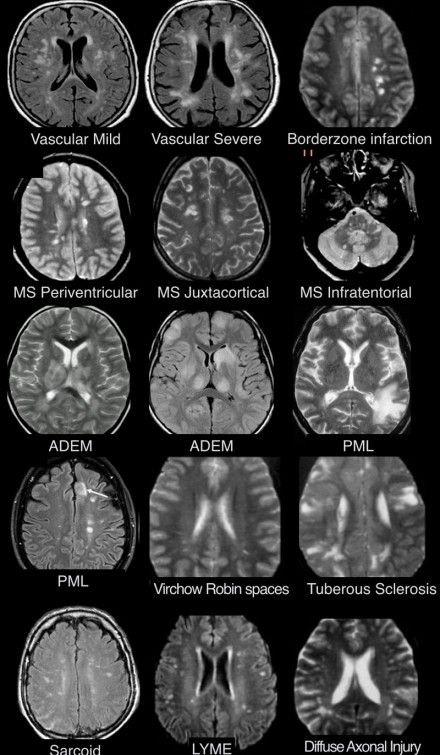

คือ เราตรวจพบก้อนเนื้อที่บริเวณแกนสมองของคนไข้

แม่คุณเป็นเนื้องอกในสมอง

เราพบว่าเจ้าก้อนเนื้อเนี่ยมีขนาดใหญ่พอสมควร